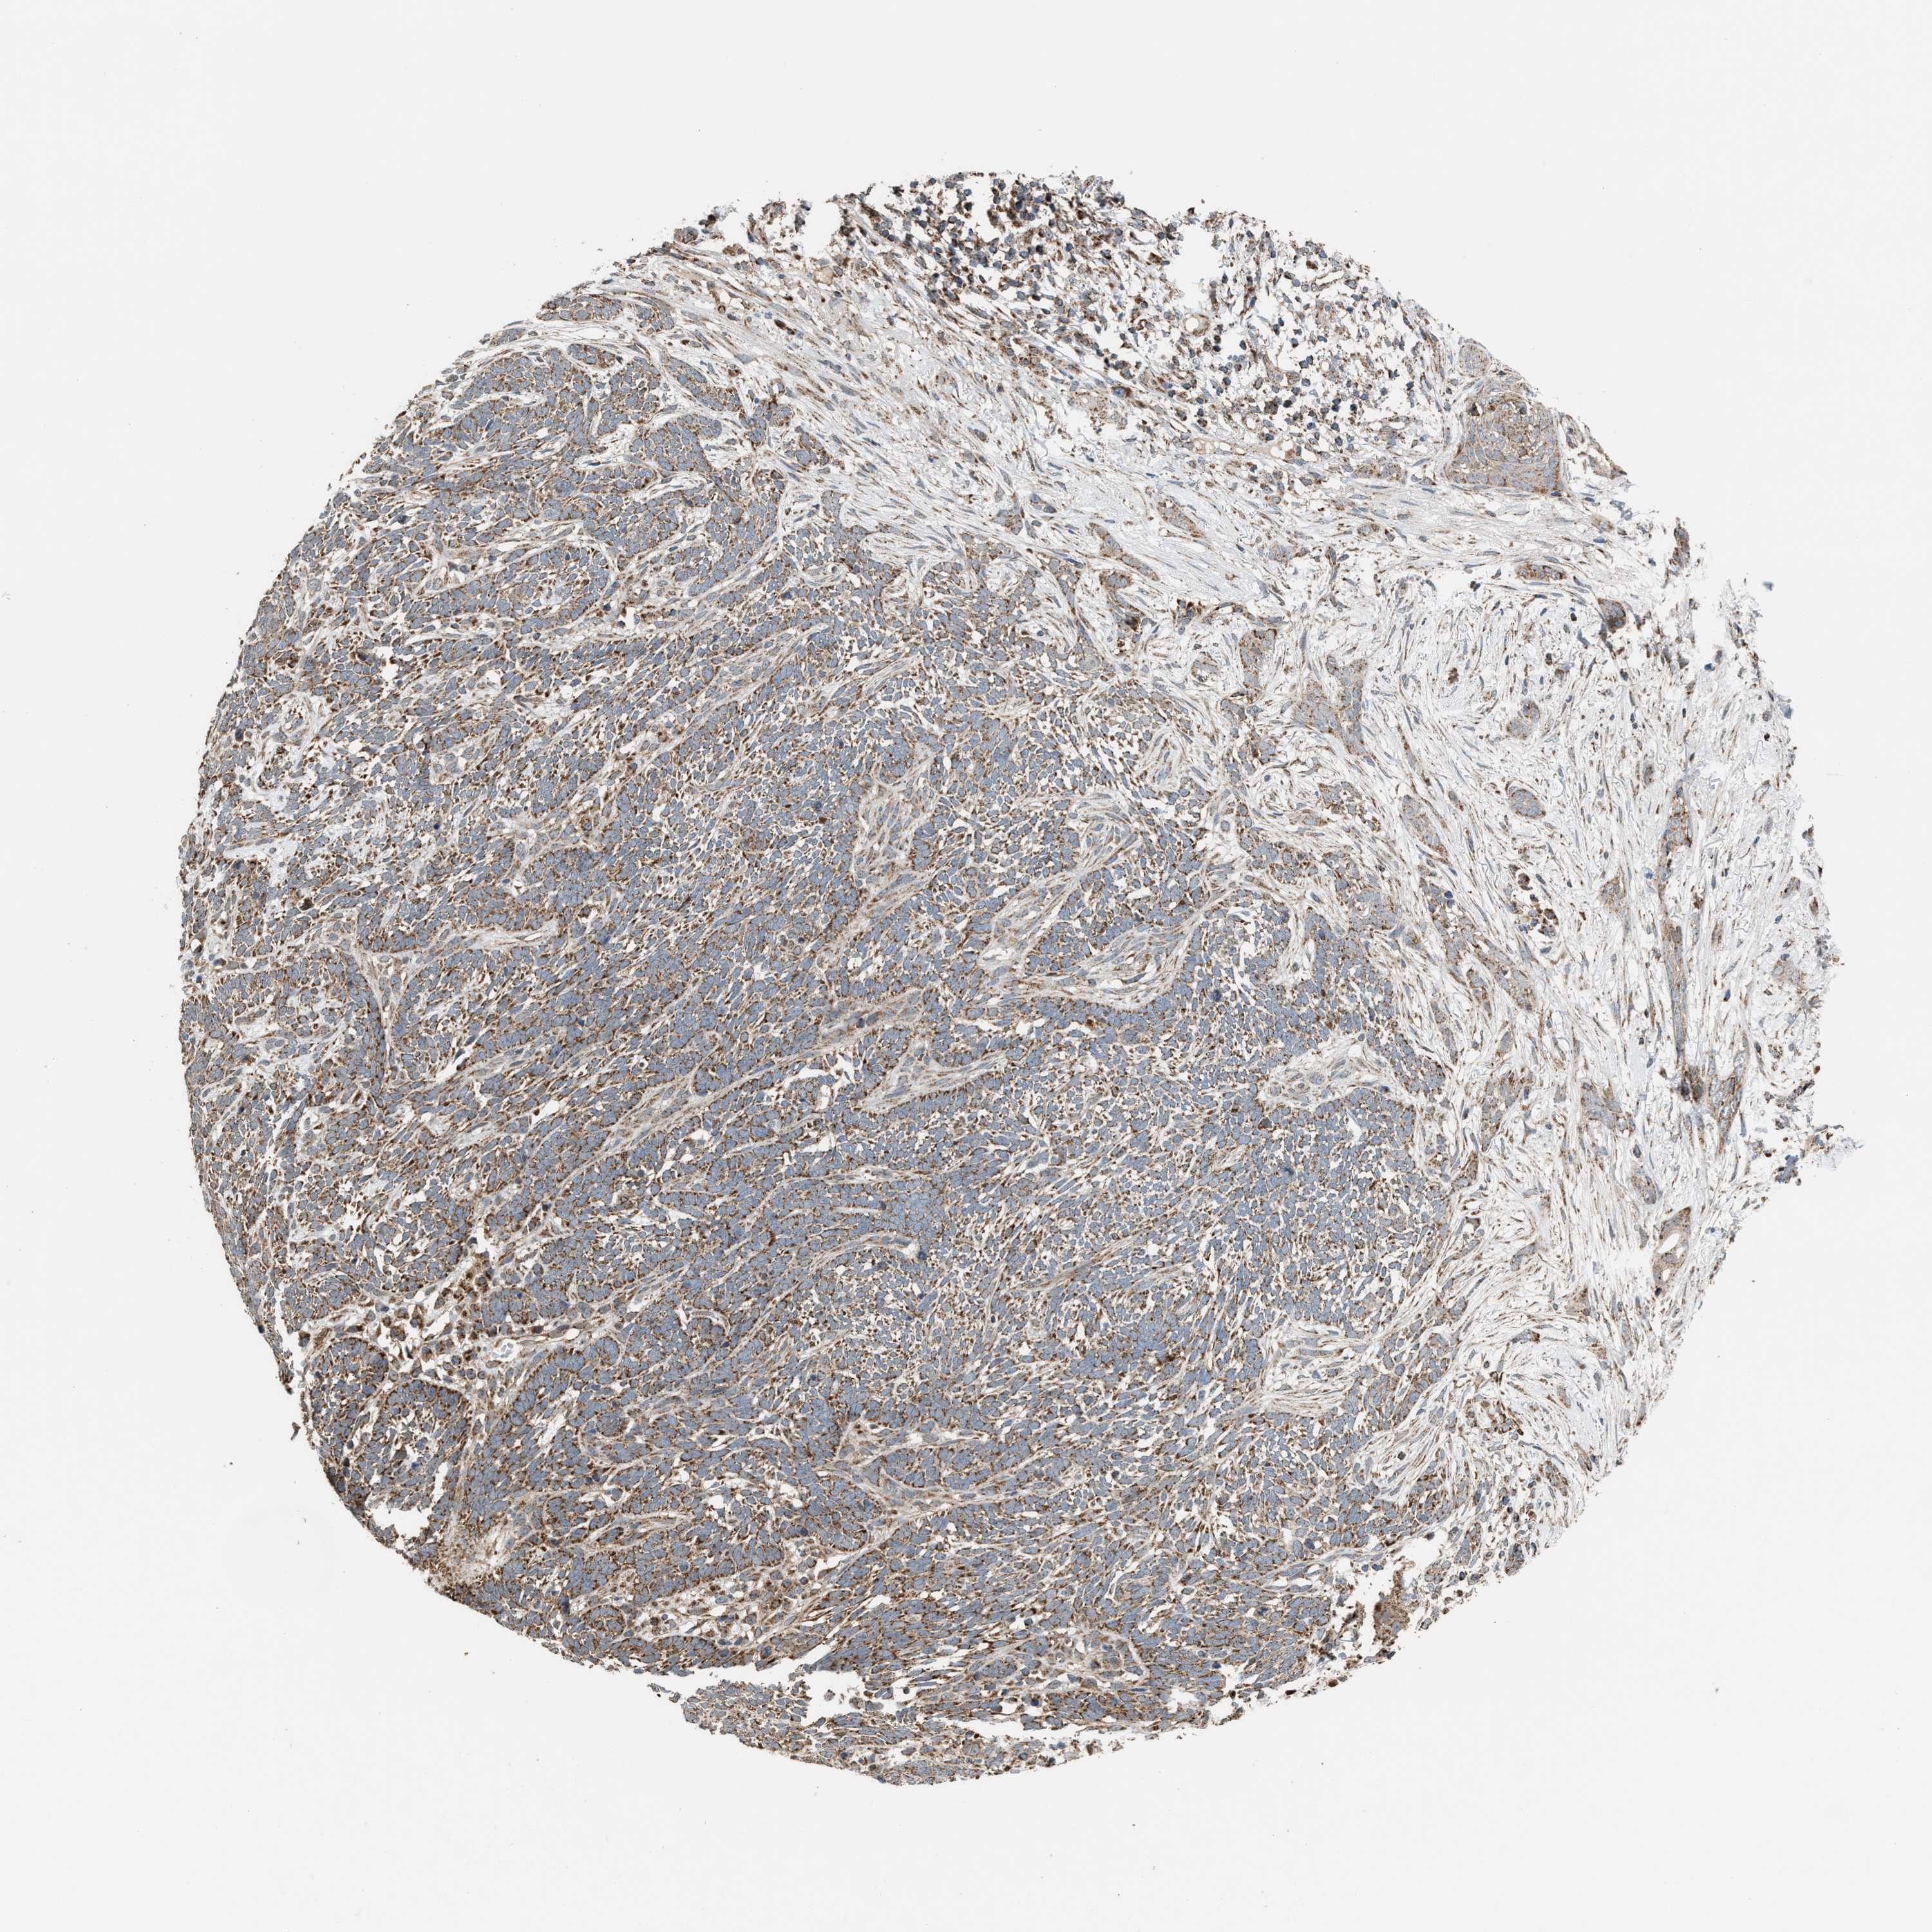

SKIN CANCER - Protein expressioni

A mouse-over function shows sample information and annotation data. Click on an image to view it in a full screen mode. Samples can be filtered based on level of antibody staining by selecting one or several of the following categories: high, medium, low and not detected. The assay and annotation is described here.

Each image is clickable and will lead to virtual microscopy that enables deeper exploration of all samples and also displays staining intensity scores, fraction scores and subcellular localization as well as patient and tissue information for each sample.

Antibody HPA024553

Staining

Not detected

Intensity

Negative

Quantity

None

Location

Basal cell carcinoma